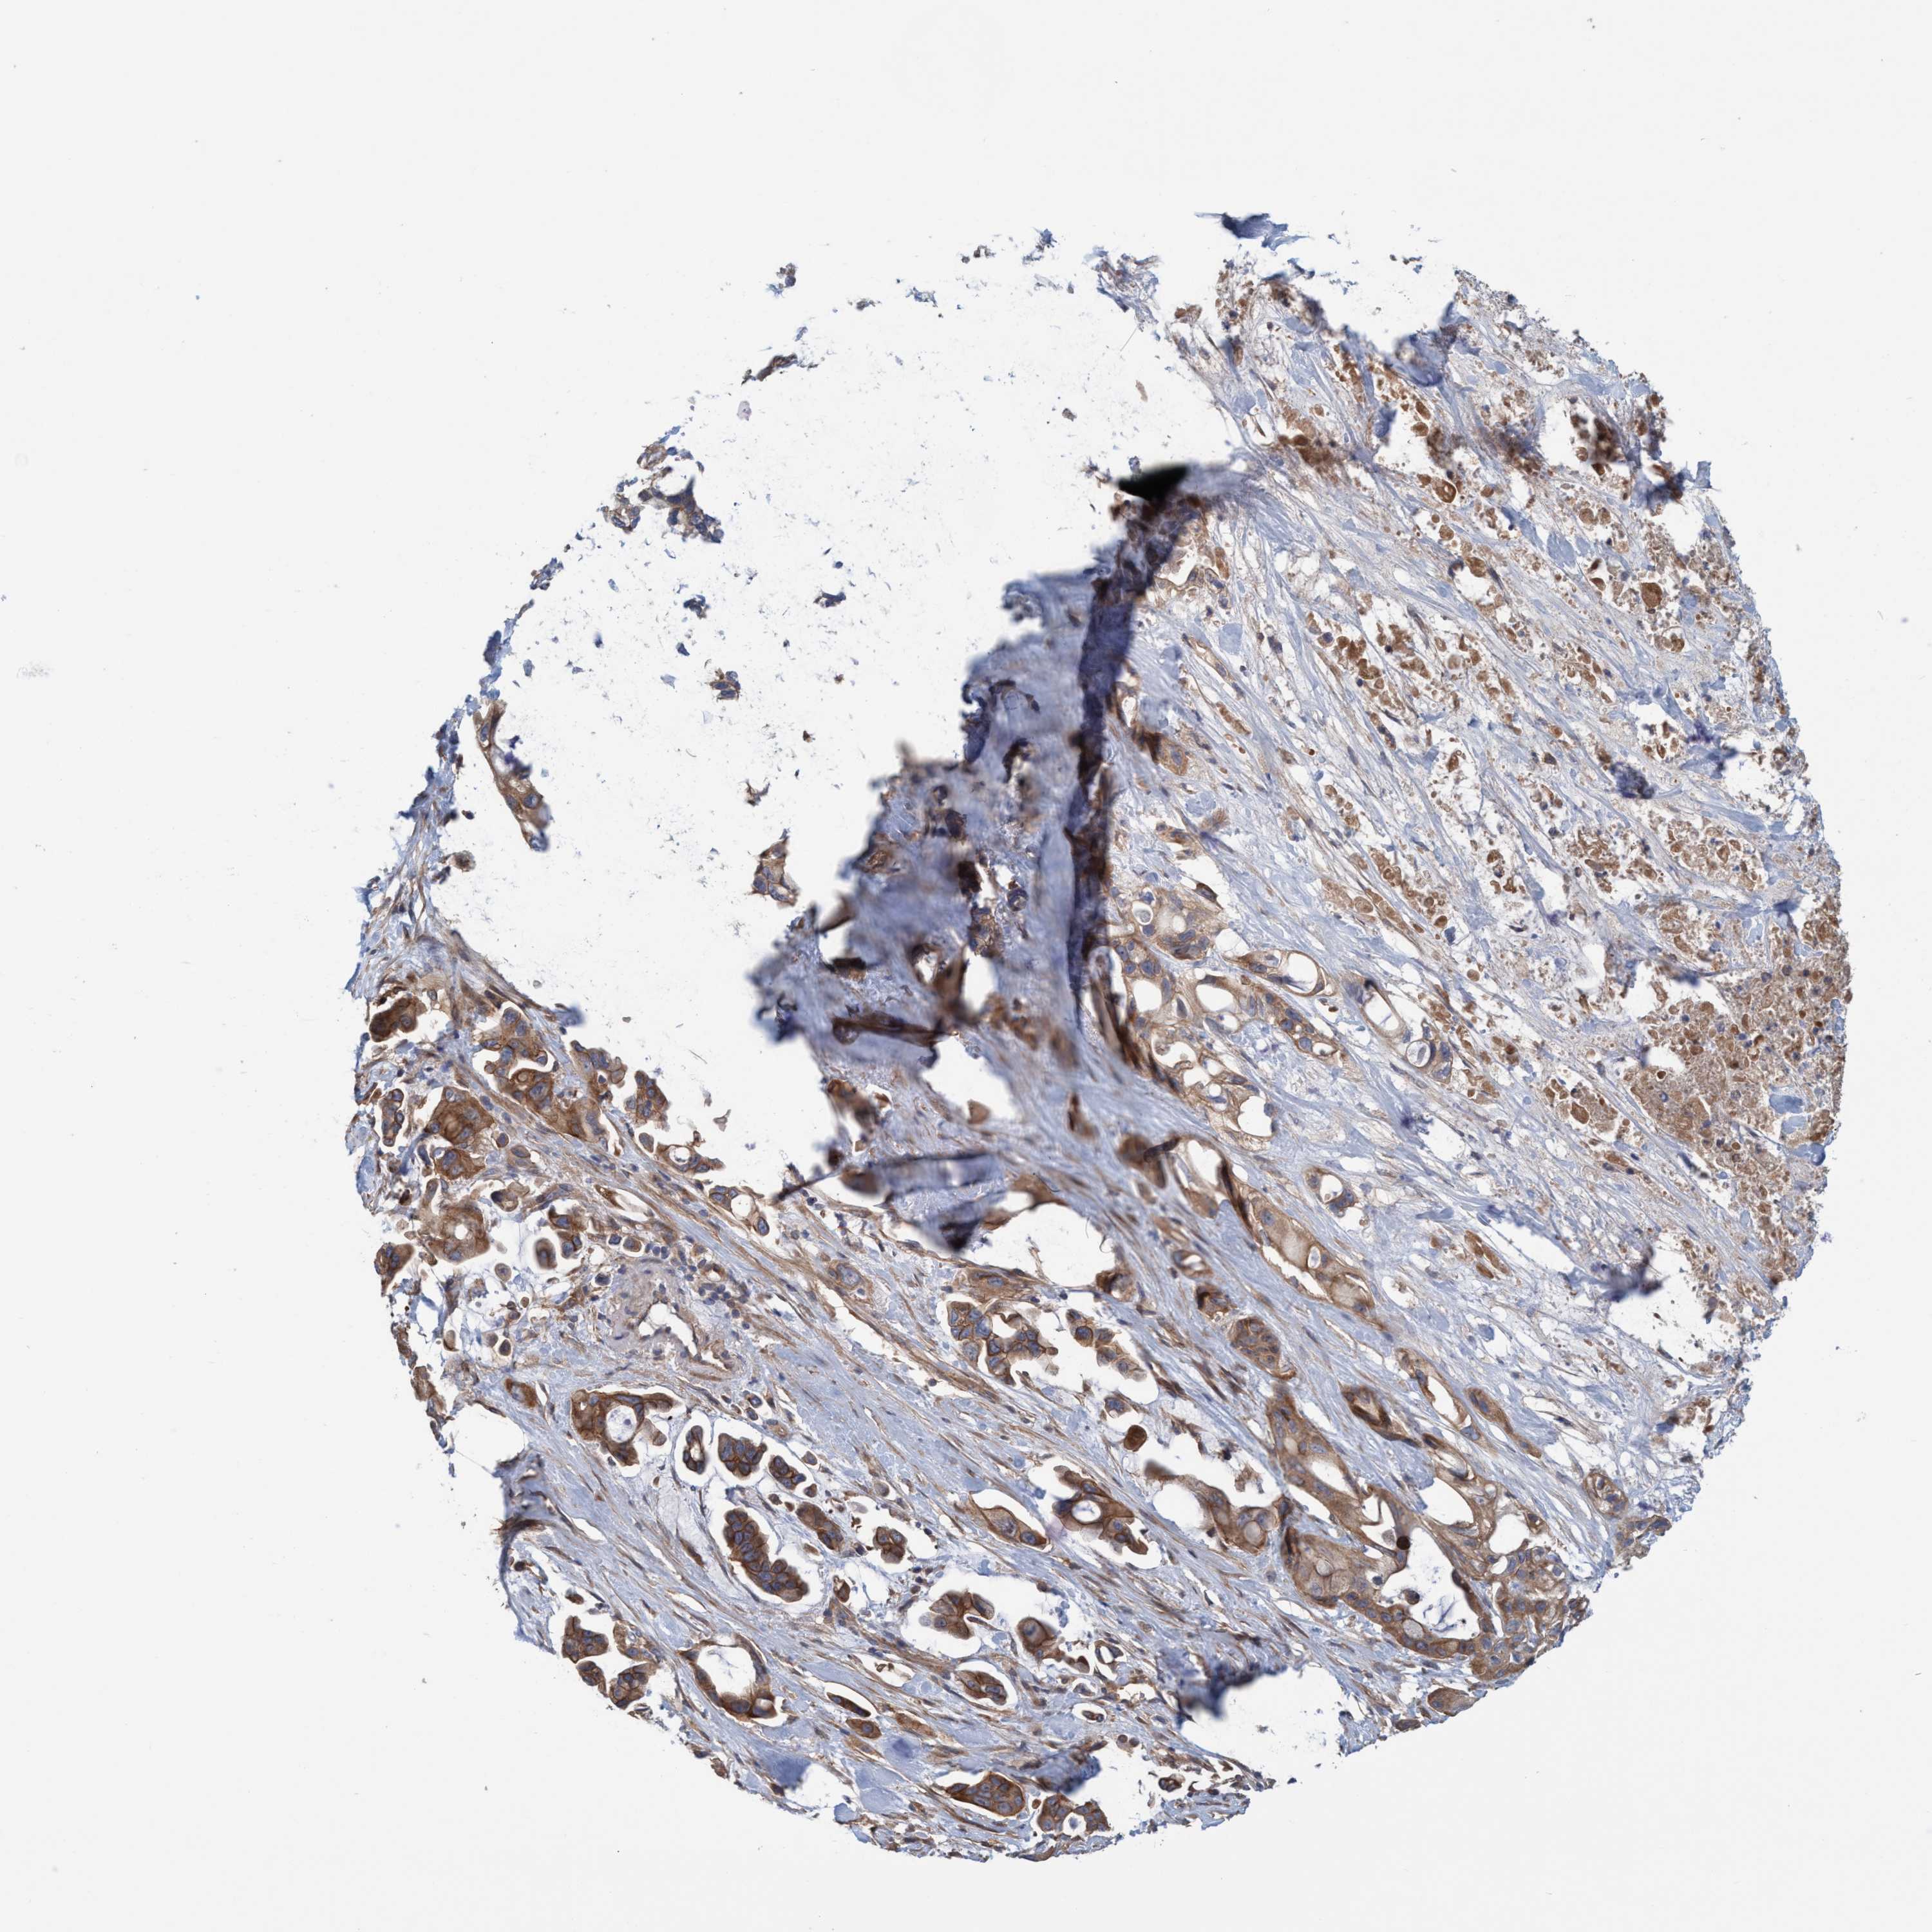

PANCREATIC CANCER - Protein expressioni

A mouse-over function shows sample information and annotation data. Click on an image to view it in a full screen mode. Samples can be filtered based on level of antibody staining by selecting one or several of the following categories: high, medium, low and not detected. The assay and annotation is described here.

Note that samples used for immunohistochemistry by the Human Protein Atlas do not correspond to samples in the TCGA dataset.

Antibody stainingi

Antibody staining in the annotated cell types in the current human tissue is reported as not detected, low, medium, or high, based on conventional immunohistochemistry profiling in selected tissues. This score is based on the combination of the staining intensity and fraction of stained cells.

Each image is clickable and will lead to virtual microscopy that enables deeper exploration of all samples and also displays staining intensity scores, fraction scores and subcellular localization as well as patient and tissue information for each sample.

Antibody HPA021421

Antibody HPA021430

Staining

High

Medium

Low

Not detected

Intensity

Strong

Moderate

Weak

Negative

Quantity

>75%

75%-25%

<25%

None

Location

Nuclear

Cytoplasmic/membranous

Cytoplasmic/membranous,nuclear

Adenocarcinoma, NOS